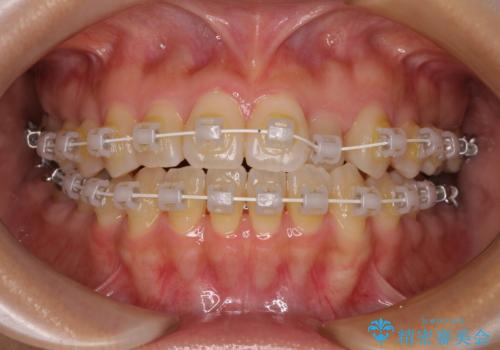

クロスバイトの前歯を改善 ワイヤー装置で楽々矯正治療

- 矯正装置

- 審美装置

- 1年4ヶ月

舌のトレーニングをしっかりと行っていただき、補綴治療も含めて1年強の短期間で治療を終えることができました。